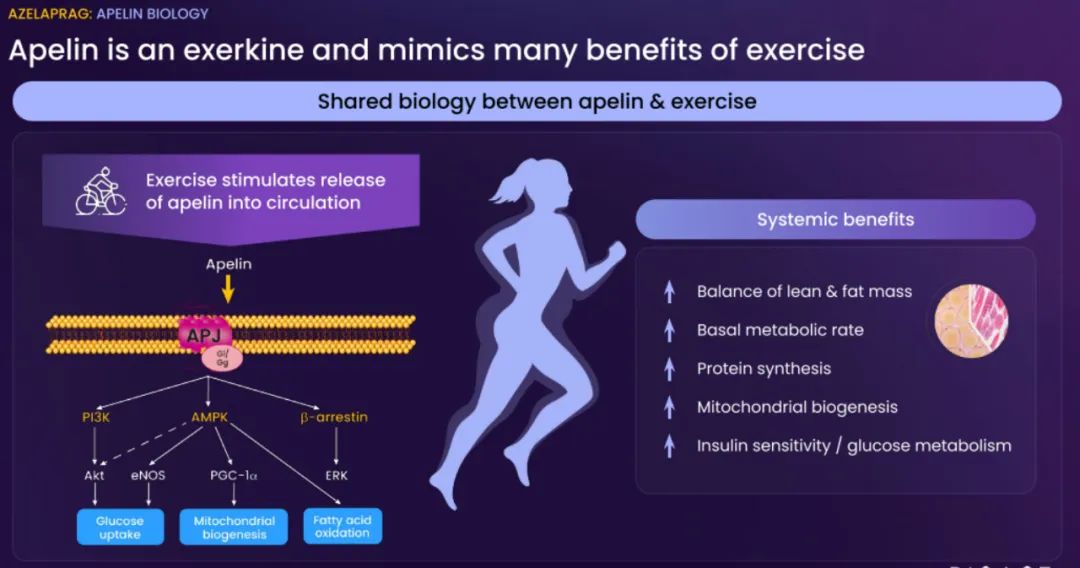

BioAge Labs的主要关注点是代谢疾病,这是全球最大的医疗保健挑战之一。BioAge Labs的主要候选产品 Azelaprag是一种口服小分子,在8个 1 期临床试验中,265 名受试者的耐受性良好。在临床前肥胖模型中,azelaprag 显示出能够使胰高血糖素样肽-1 受体 (GLP-1R) 激动剂诱导的体重减轻增加一倍以上,同时恢复健康的身体成分并改善肌肉功能。

这些临床前结果得到BioAge Labs在卧床老年人中进行的 1b 期临床试验的支持,在该试验中,BioAge Labs观察到在 10 天内接受 azelaprag 治疗的受试者的肌肉萎缩减少、肌肉质量保持良好并且新陈代谢得到改善。